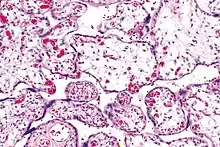

| Micrograph of villous immaturity. H&E stain. | |

Placental villous immaturity is chorionic villous development that is inappropriate for the gestational age.

Immature chorionic villi are larger and have more central blood vessels; thus, the diffusion distance for gas and nutrient exchange is larger and, therefore, placental function is impaired.

Low mag.